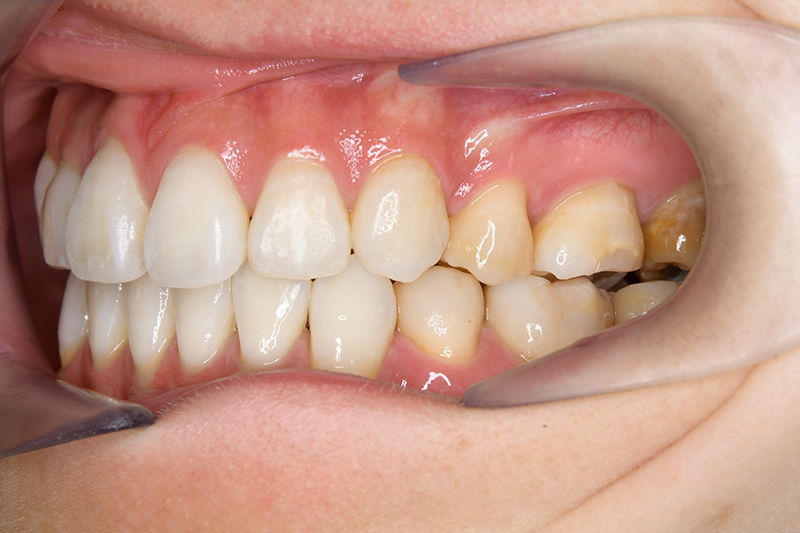

動的治療終了時

FP・IOP

批評・予后 治療後、緊密な咬合の確立と共に大幅な切歯の後退によって主訴である口元の突出感と口唇閉鎖不全の改善が得られた。